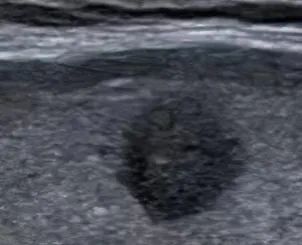

通常结节至少要>1公分以上才能通过临床医生的触诊,可以初步诊断出。随着医学技术的发展,在各种检查手段中,超声机器能更加方便准确地检测出甲状腺结节的大小、形态、位置、血流等情况,更加方便临床医生及患者了解自己结节的情况。

从超声报告中观察,通常甲状腺结节具备几个要素,超声的恶性评分会逐渐增高,从而在结节分级中体现出来。

1、结节内有微钙化;

2、结节与周围甲状腺组织界限不清;

3、纵横比大于1或不规则形的结节;

4、低回声或极低回声;

5、周边及结节內部少量血流信号的“乏血流”改变;